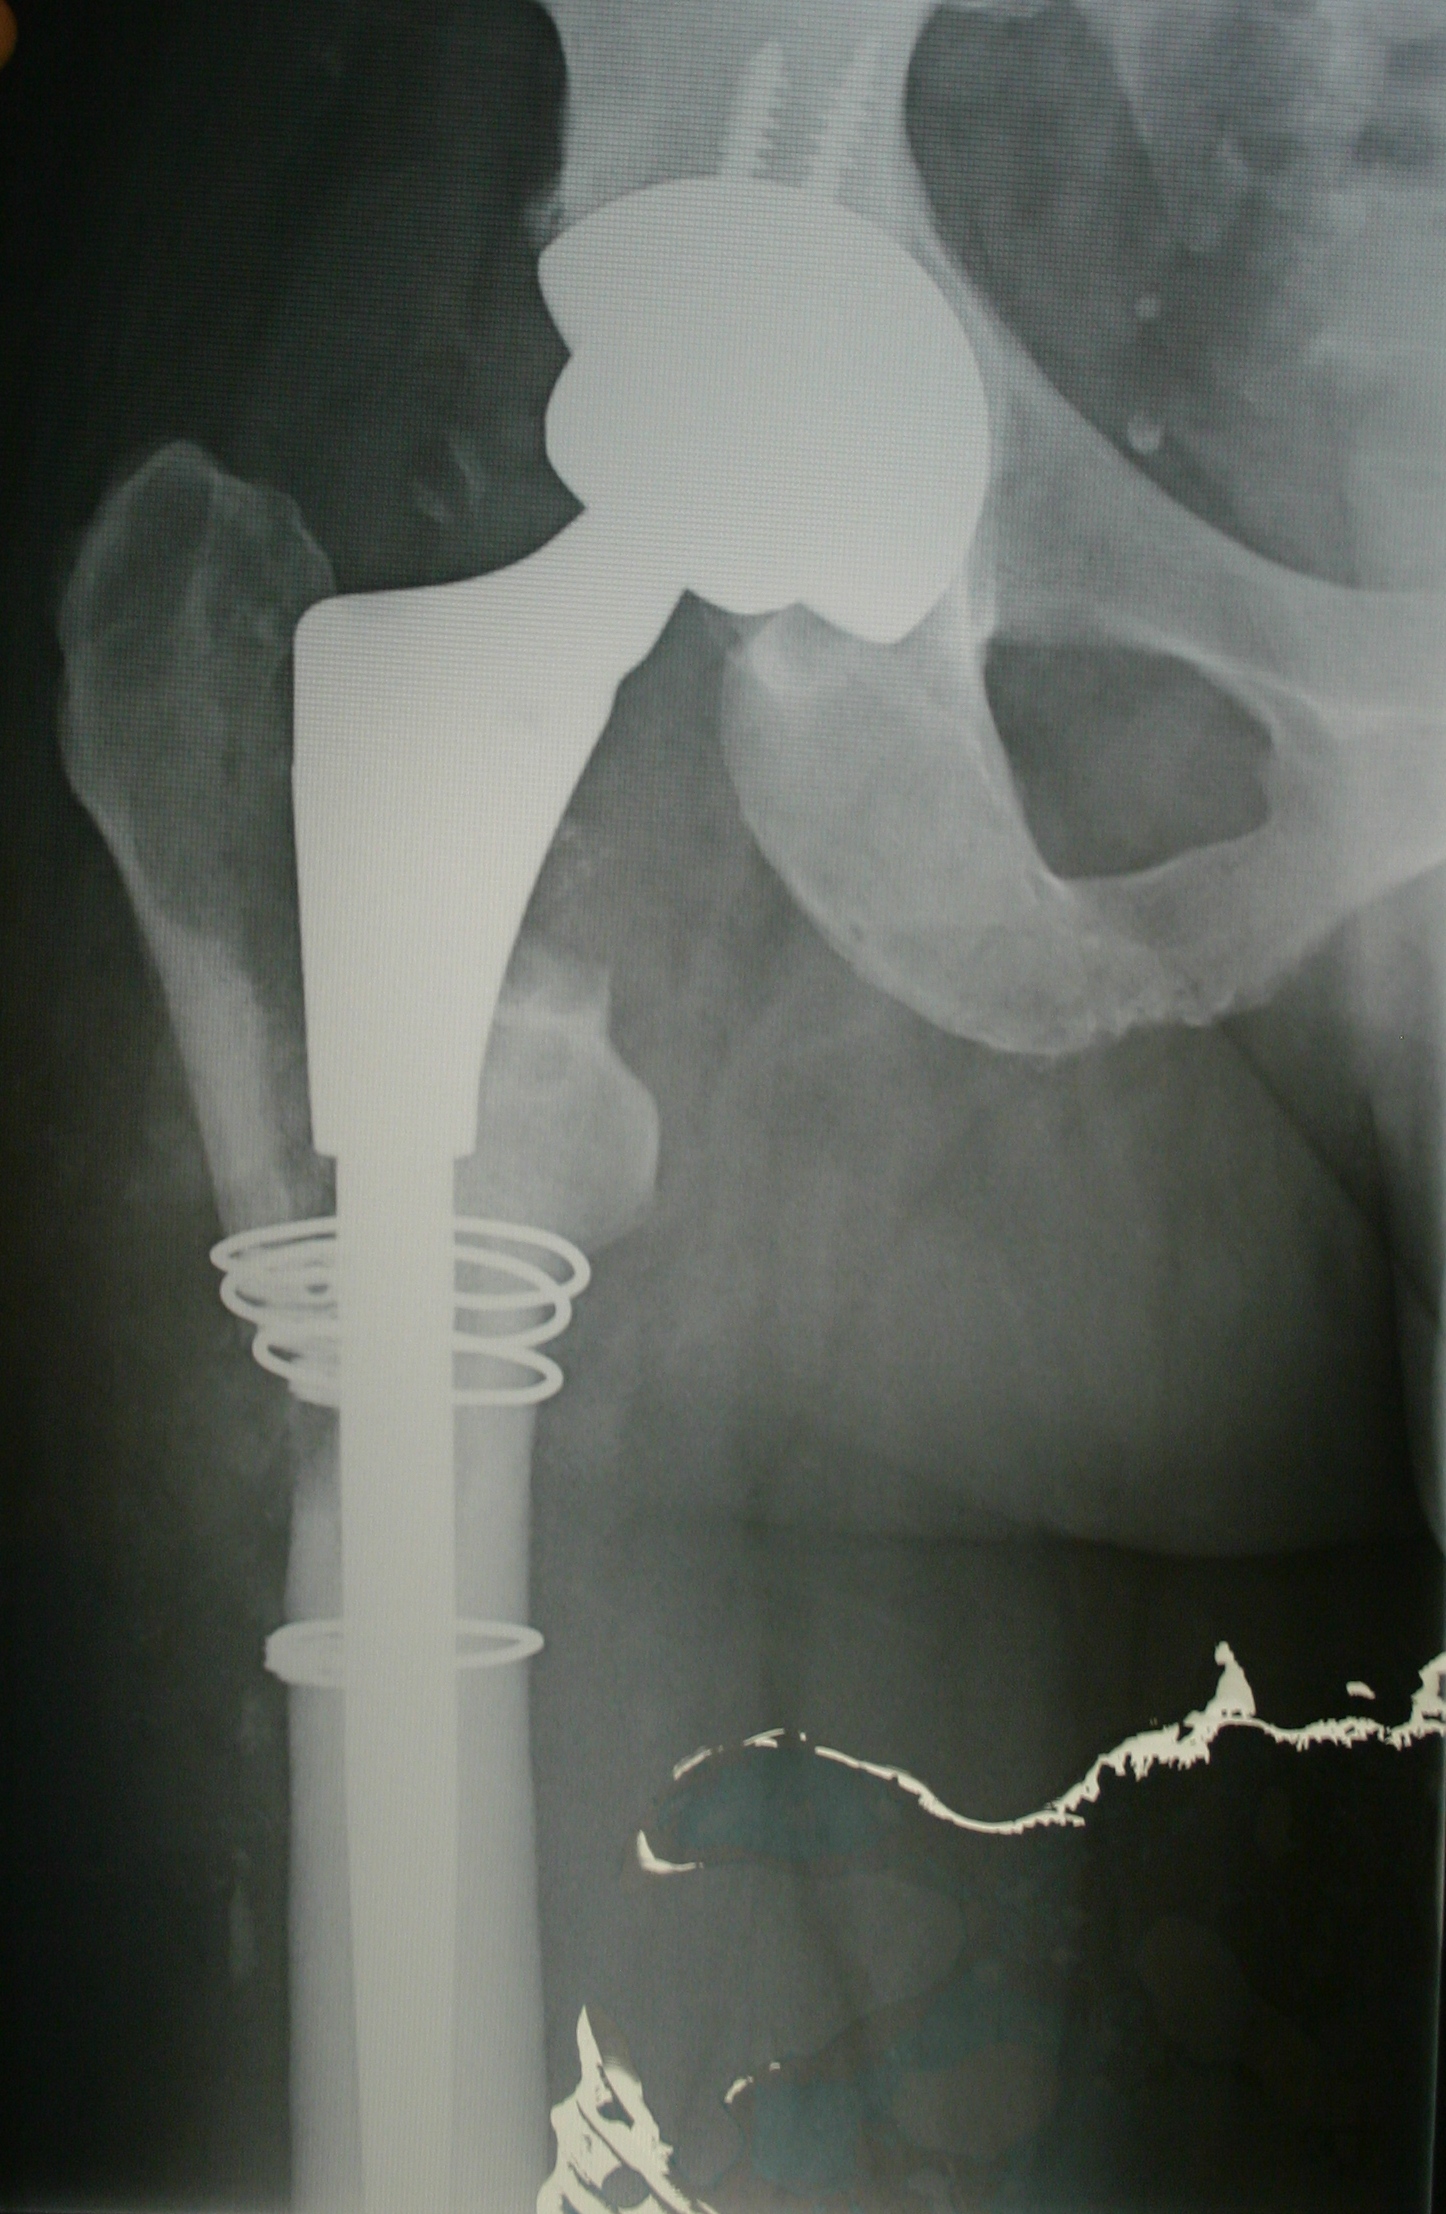

Figure 2: The uncemented implant shown has its femoral component made of cobalt chromium with titanium. An acetabular cup covering a ceramic head is temporarily held in place with a screw.

[In this X-Ray (mine) the femoral stem and acetabular cup are both cementless, press-fit.]

The alternative to cemented fixation is uncemented fixation. The metal stem is sometimes coated with a porous coating. The non-cemented stems have a coarse and gritty exterior. Research has shown that bone will attach to a metal implant if the surface of the metal has a surface topography that is conducive to attracting new bone growth. The porous coating is generally either pure titanium or a substance known as hyroxyapatite. Hyroxyapatite is derived from the mineral portion of the bone. The coarse and gritty exterior of the stem allows the bone to essentially grow into the surface of the implant. The porous coating, when combined with the surface topography of the stem implant, is conducive to bone growth, allowing it to achieve fixation within the bone.